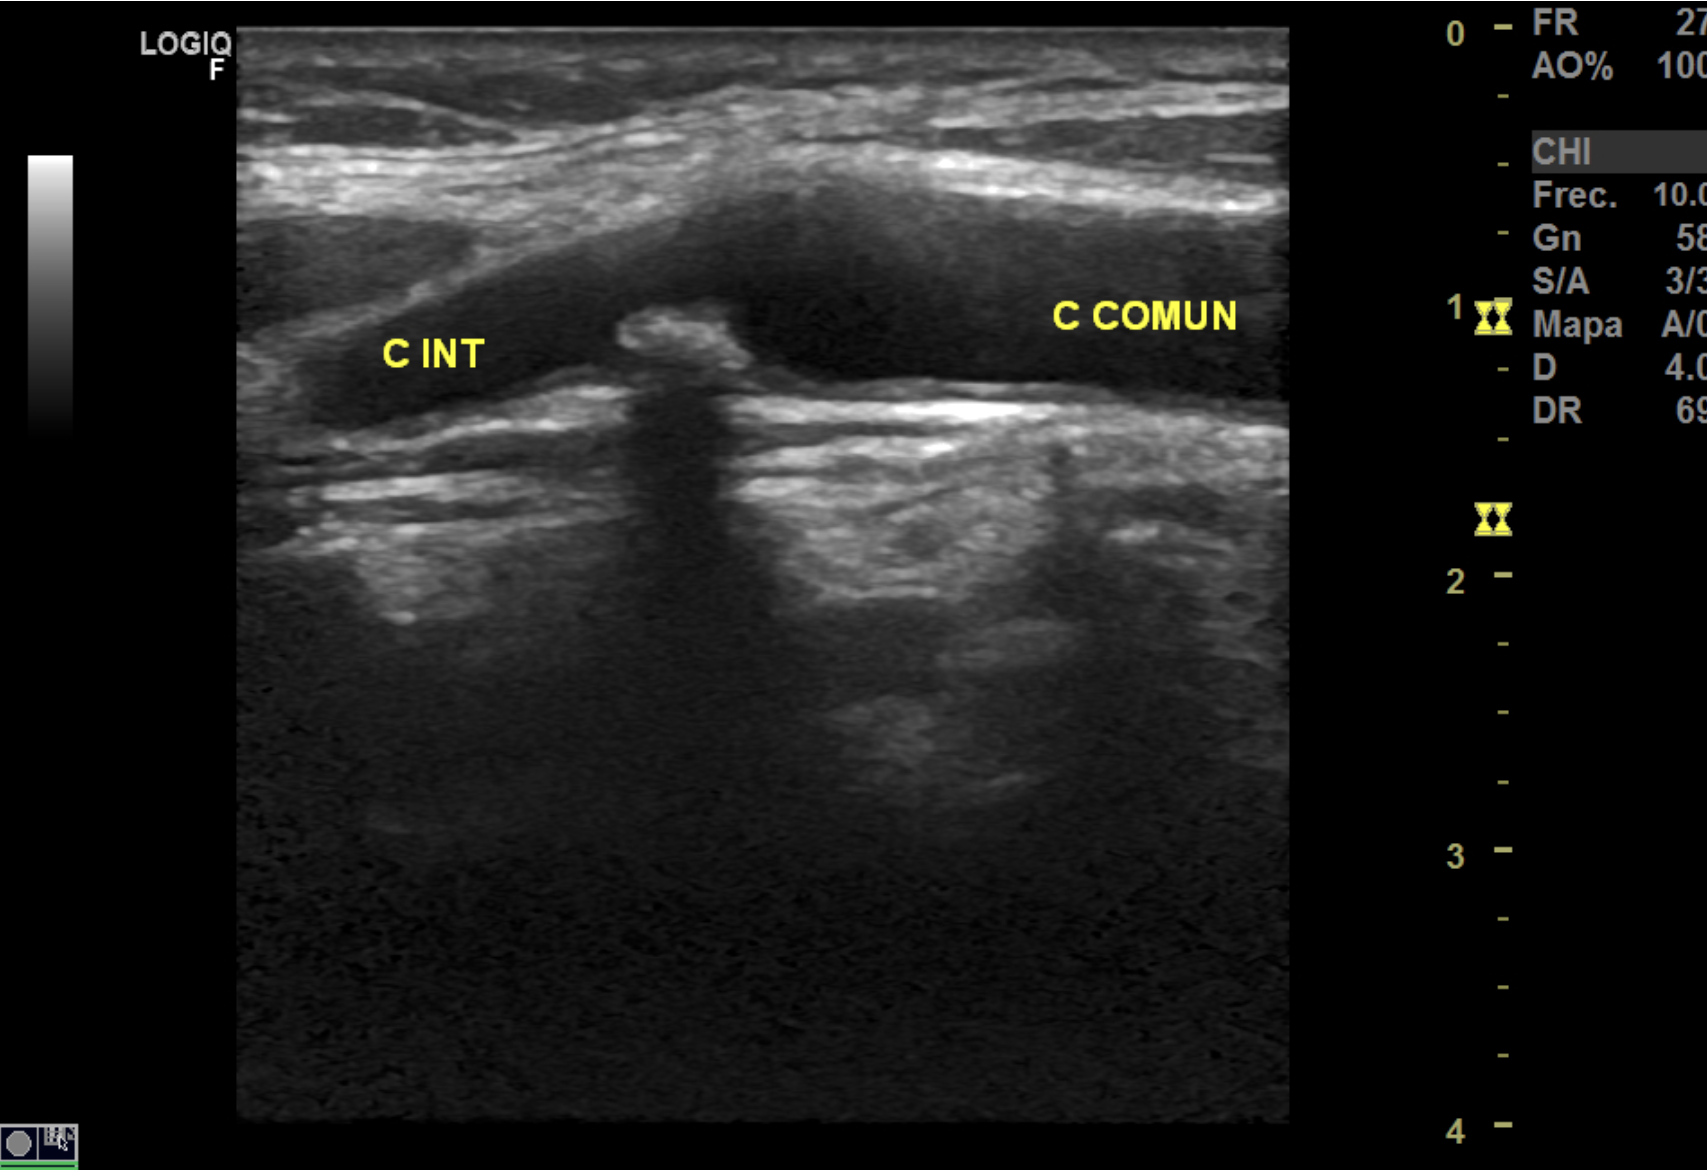

Hallazgos ecográficos

La ecografía Doppler carotídea realizada en AP mostró placas hiperecoicas y calcificadas en ambas carótidas comunes, con estenosis bilateral de aproximadamente 20% del lumen. Carótidas externas e internas permeables y morfología normal.

La ecografía tiroidea realizada en atención primaria, extendiéndose un poco más allá del órgano en estudio, permitió detectar esta enfermedad subclínica, facilitando una actuación temprana y reduciendo el riesgo de futuros eventos cerebrovasculares.